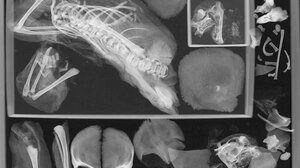

Ανατριχιαστικά ευρήματα σε μούμια έφηβης που πέθανε στην γέννα πριν από 1.500 χρόνια ΚΟΣΜΟΣ 30.12.2023Ανατριχιαστικά ευρήματα σε μούμια έφηβης που πέθανε στην γέννα πριν από 1.500 χρόνια